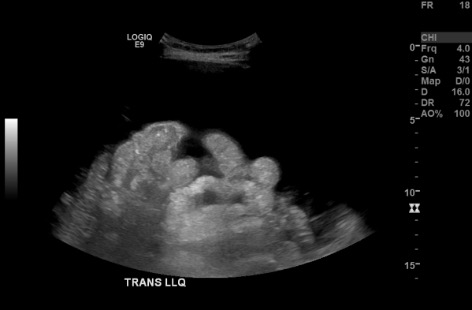

US survey — LLQ fluid pocket + Doppler

Color Doppler US of LLQ showing vessel check at planned paracentesis access site B-mode US measuring distance from skin to ascitic fluid pocket in LLQ B-mode US confirming no vessels along needle trajectory in LLQ